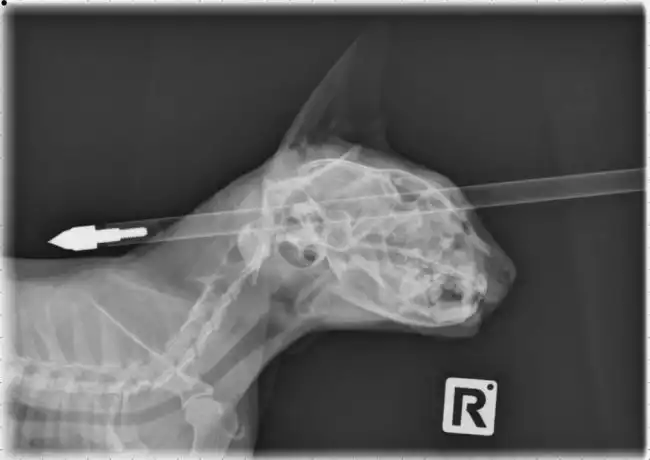

Ветеринары спасли кошку

Животинке очень повезло, что ранение не задело жизненно-важные органы.

жизненно-важные органы не задеты...

что за жееесть? кто блин выстрелил в кота ?? в голову!

бедный китюля

А гдеж тогда у него мозг, если он не был задет?...